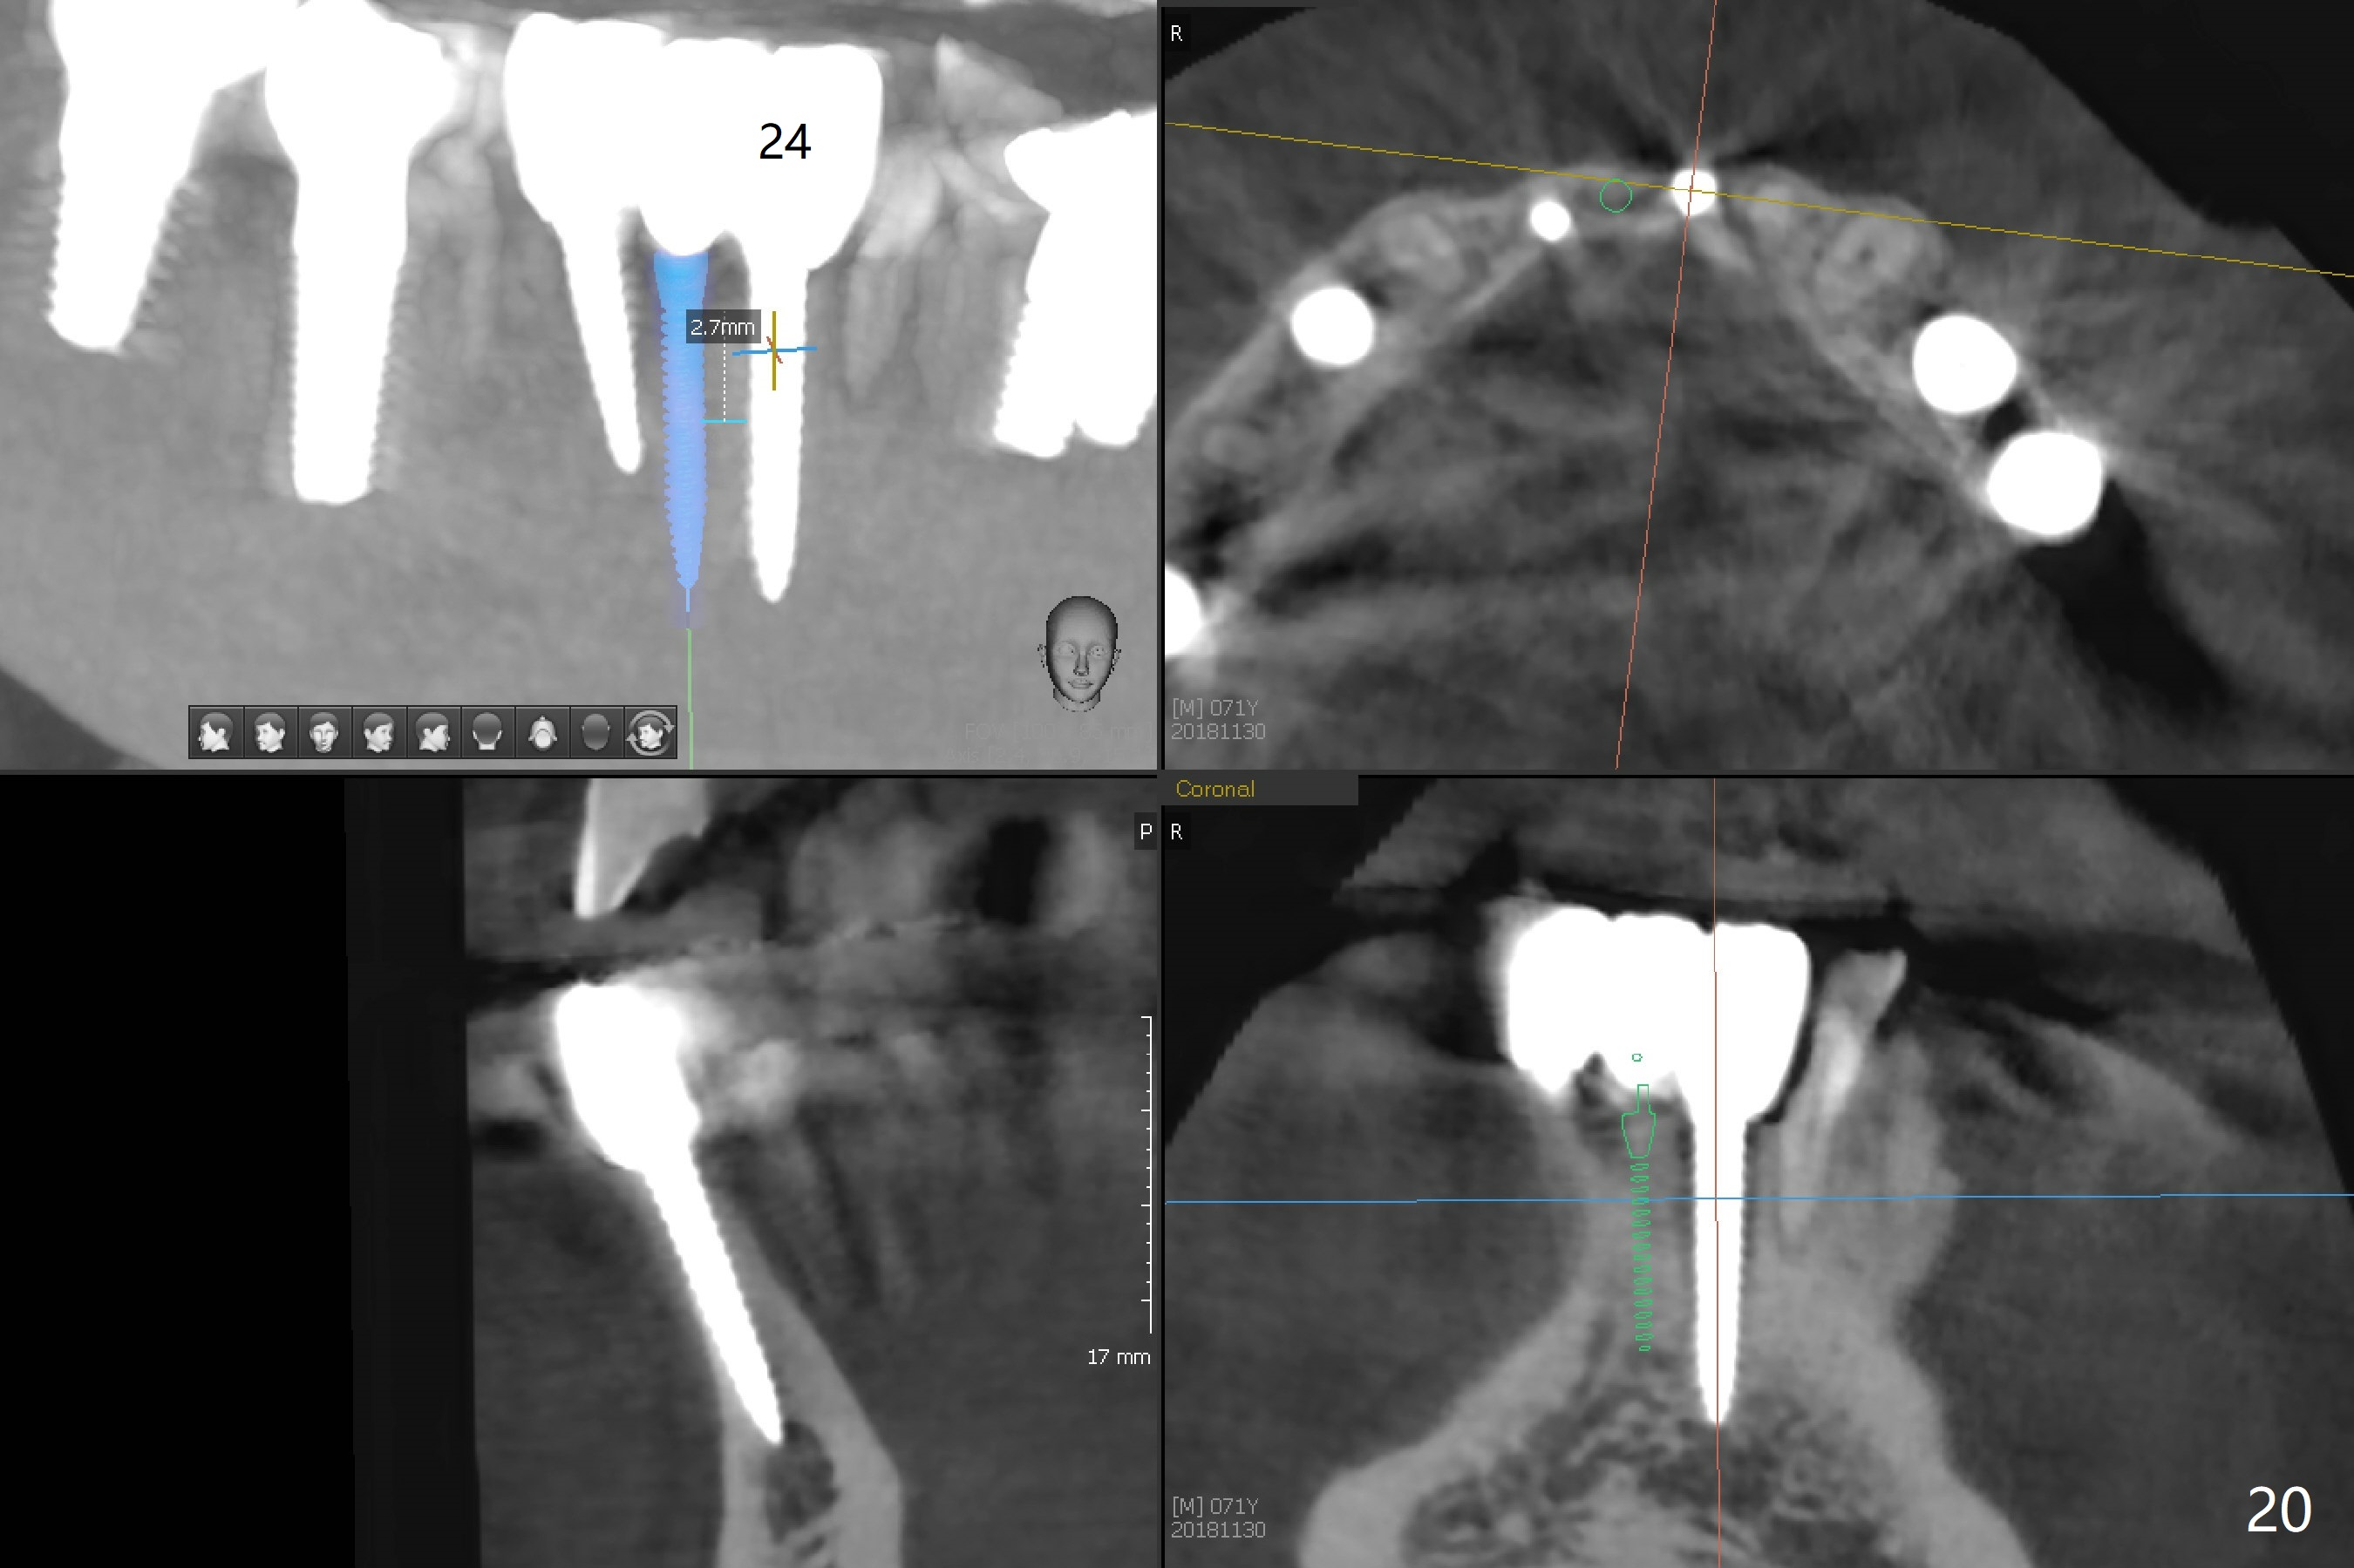

The infection persists at #26 four years 8 months post cementation (Fig.16 *). CBCT is taken. In fact the implant at #26 was placed lingual (Fig.17), while that at #24 buccal (Fig.20). The 2nd option is to remove the implant at #26 and place a 2 mm one at #25 (Fig.18,19). Fabricate a 3-unit cantilever FPD. Take 5x5 cm CT with 1.2 mm drill in place for 10 mm. Change the trajectory and position if necessary.